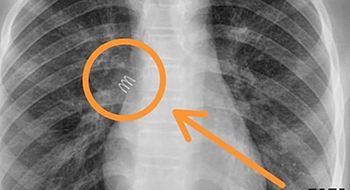

Расшифровка цифровых кодов флюорографии с примерами

01 - Кольцевидная тень (полость).

22 - Инородное тело (проецируется на легочную ткань, тень средостения в мягких тканях).

02 - Затемнение в легочной ткани (инфильтрация,ателектаз, округлая тень, среднедолевой синдром и др.).

03 - Очаговые тени в легочной ткани.

04 - Расширение тени средостения, в том числе увеличение размеров корня.

05 - Плевральные выпоты.

06 - Фиброзные изменения в легочной ткани (выраженные).

07 - Фиброзные изменения в легочной ткани (ограниченные).

08 - Повышение прозрачности легочной ткани (эмфизема локальная и распространенная).

09 - Изменения плевры (сращения, плевральные наслоения, обызвествления) выраженные.

10 - Изменения плевры (сращения, плевральные наслоения, обызвествления) ограниченные.

11 - Петрификаты крупные в легочной ткани - множественные (5 и более).

12 - Петрификаты крупные в корнях - множественные (5 и более).

13 - Петрификаты мелкие в легочной ткани - множественные (5 и более).

14 - Петрификаты мелкие в корнях - множественные (5 и более).

15 - Петрификаты крупные в легочной ткани - единичные.

16 - Петрификаты крупные в корнях - единичные.

17 - Петрификаты мелкие в легочной ткани - единичные.

18 - Петрификаты мелкие в корнях - единичные.

19 - Изменения диафрагмы, не связанные с плевральной патологией (диафрагмальная грыжа, высокое стояние диафрагмы и т. д.).

20 - Состояние после операции на легком.

21 - Изменения скелета грудной клетки (сколиоз, кифосколиоз, костная мозоль, добавочное ребро, остеофиты и т. д.).

23 - Сердечно-сосудистая патология.

24 - Прочие - добавочная доля.

25 - Норма.

26 - Брак.

Примечания:

При сочетании нескольких из перечисленных изменений каждое из них отмечается соответствующим кодом в каждой графоклетке.

Локализация, протяженность изменений отмечается дробью по второй графоклетке 1; 2; 3; 4; в числителе - правое легкое, в знаменателе - левое легкое (по полям).

Номер шифра легочных полей: 1 - первое, 2 - второе, 3 - третье, 4 - первое и второе, 5 - первое и третье, 6 - второе и третье, 7 - первое, второе и третье.

В третьей графоклетке вместо подписи врача подставляют личный номер рентгенолога.

Вызов на контрольное рентгеновское дообследование отмечается в четвертой графоклетке цифрой 1.